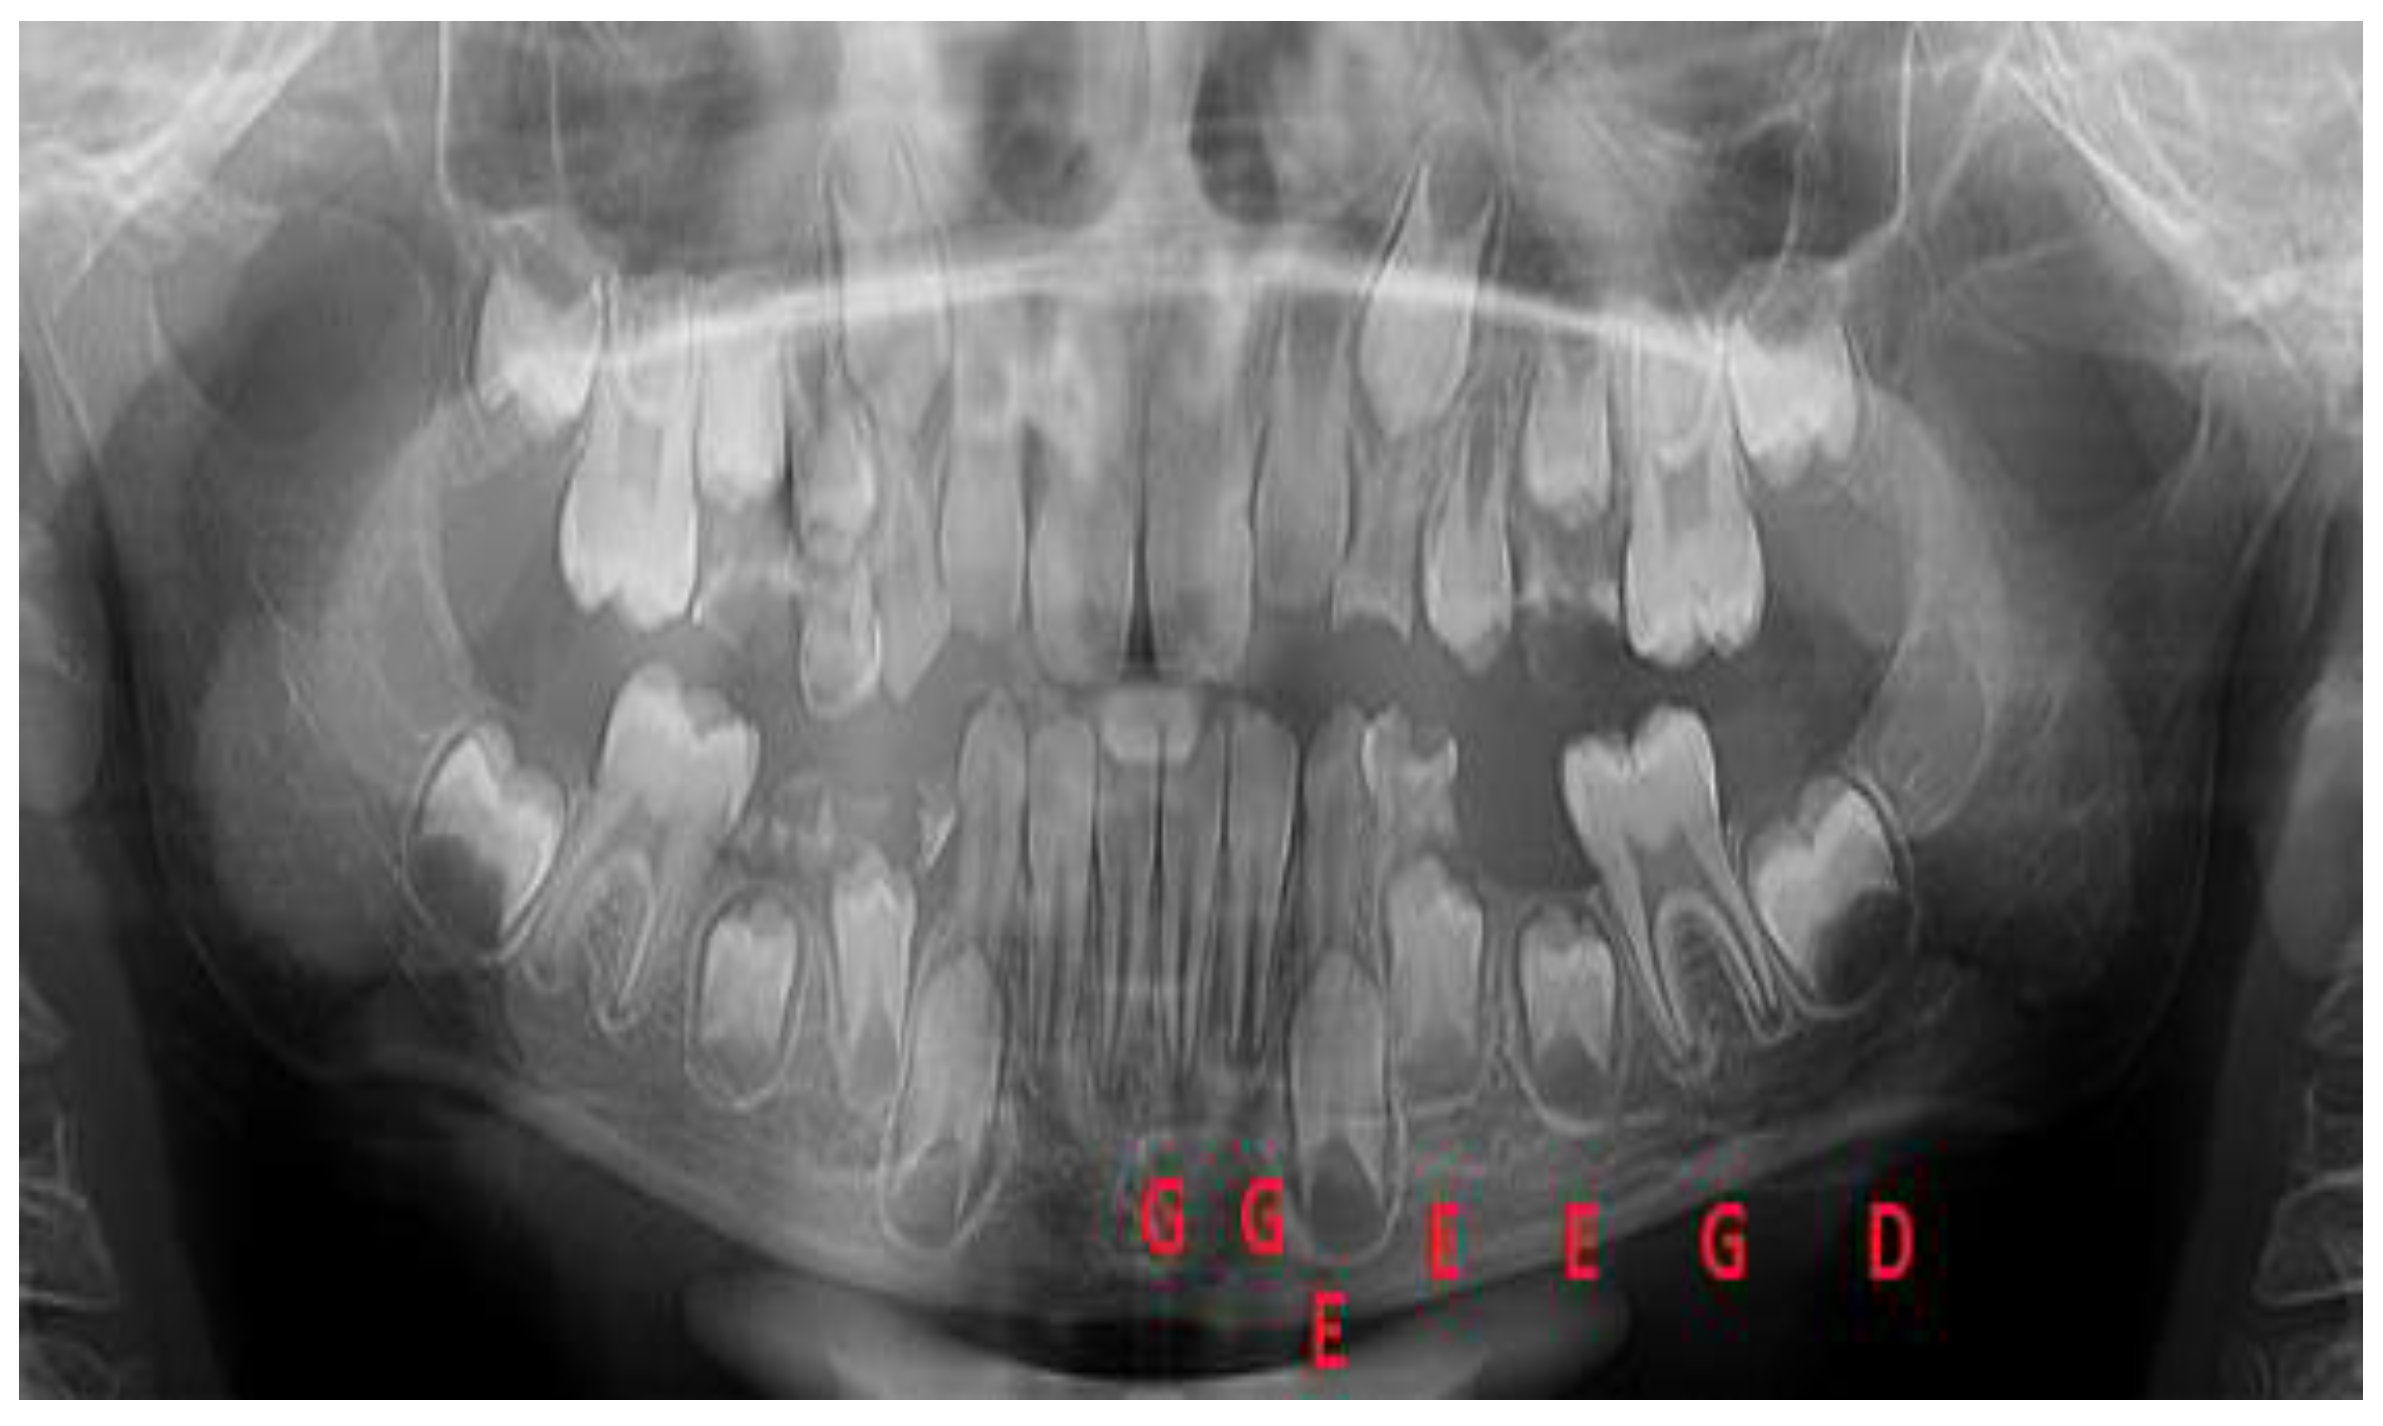

![]() |